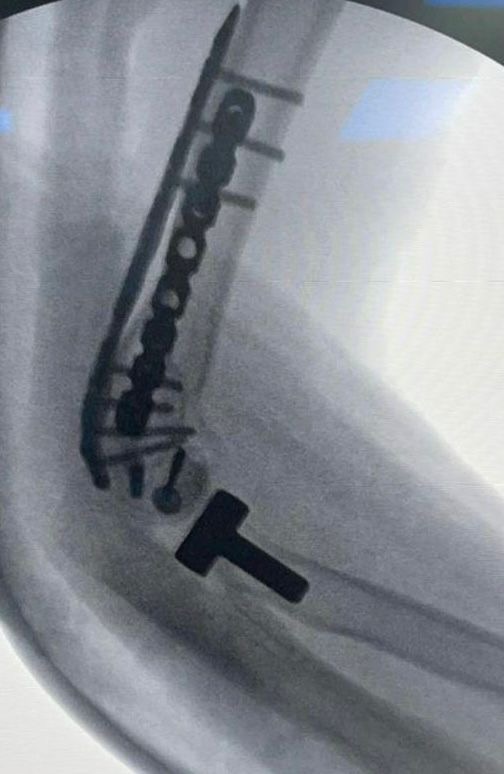

في إنجاز طبي يعد الأول من نوعه على مستوى المنطقة الشرقية، نجح فريق طبي في مستشفى الملك فهد الجامعي بالخبر – التابع للمدينة الطبية الأكاديمية بجامعة الإمام عبدالرحمن بن فيصل – في إجراء عملية جراحية نادرة ومعقدة، تمثلت في زراعة مفصل المرفق وترميم الأربطة المحيطة لشاب في مقتبل العمر، بعد أن تعرّض لإصابة خطيرة نتج عنها كسر مضاعف وفقدان جزء كبير من المفصل وتهتك في الأنسجة المحيطة.

قاد الفريق الطبي للعملية الدكتور سعد القحطاني – رئيس قسم العظام واستشاري جراحة العظام والأطراف العلوية – حيث أوضح أن الفريق تعامل مع الحالة منذ بدايتها بشكل دقيق، بدءًا من فحص المريض في العيادة وإجراء الفحوصات المخبرية والأشعات ، وصولًا إلى التعاون مع الدكتور محمد بارجاء من قسم الهندسة الطبية الحيوية للاستعانة بتقنية الطباعة ثلاثية الأبعاد في تحديد حجم الجزء المفقود من المفصل بدقة عالية.

وأشار الدكتور القحطاني إلى أن مثل هذه الحالات غالبًا ما يتم علاجها عبر تركيب مفصل صناعي، إلا أن صغر سن المريض جعل الفريق يتخذ قرارًا استثنائيًا بزرع عظم ومفصل من متبرع ، مع ترميم الأربطة المحيطة للمفصل، بهدف الحفاظ على وظيفة المرفق ومنح المريض أفضل نتيجة ممكنة.